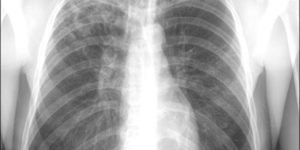

При проведении рентгена грудной клетки доктора, прежде всего, просматривают состояние корней легких. Это так называемы «врата» в главный орган дыхания. Если никаких проблем с ними нет, то на снимке они будут в нормальном состоянии, без уплотнений. Большое значение имеет и расположение корней.

Они делятся на три части: верхний, средний и нижний сектор. Правый корень по форме напоминает кривую ленту, сужающуюся книзу, он слабо выражен на снимках. Его верхняя часть находится на уровне второго межрёберья. Вершина левого корня находится на одно ребро выше, чем правый. Сам корень частично скрывает тень от сердца.

В норме на рентгенограмме они не увеличены, на их фоне не видны никакие образования. Само расположение корней также имеет значение.

Корни делят на три сектора — верхний, средний и нижний. Правый корень напоминает искривлённую ленту, которая средне выражена и сужается книзу.

Верхняя часть этого корня расположена на том же уровне, что и передний отрезок второго ребра — второго межрёберья. Верхняя часть левого корня расположена на одно ребро выше правого, а сам он частично скрыт тенью от сердца.

Ширина артериального ствола корней, в большинстве случаев, не превышает 15 миллиметров.